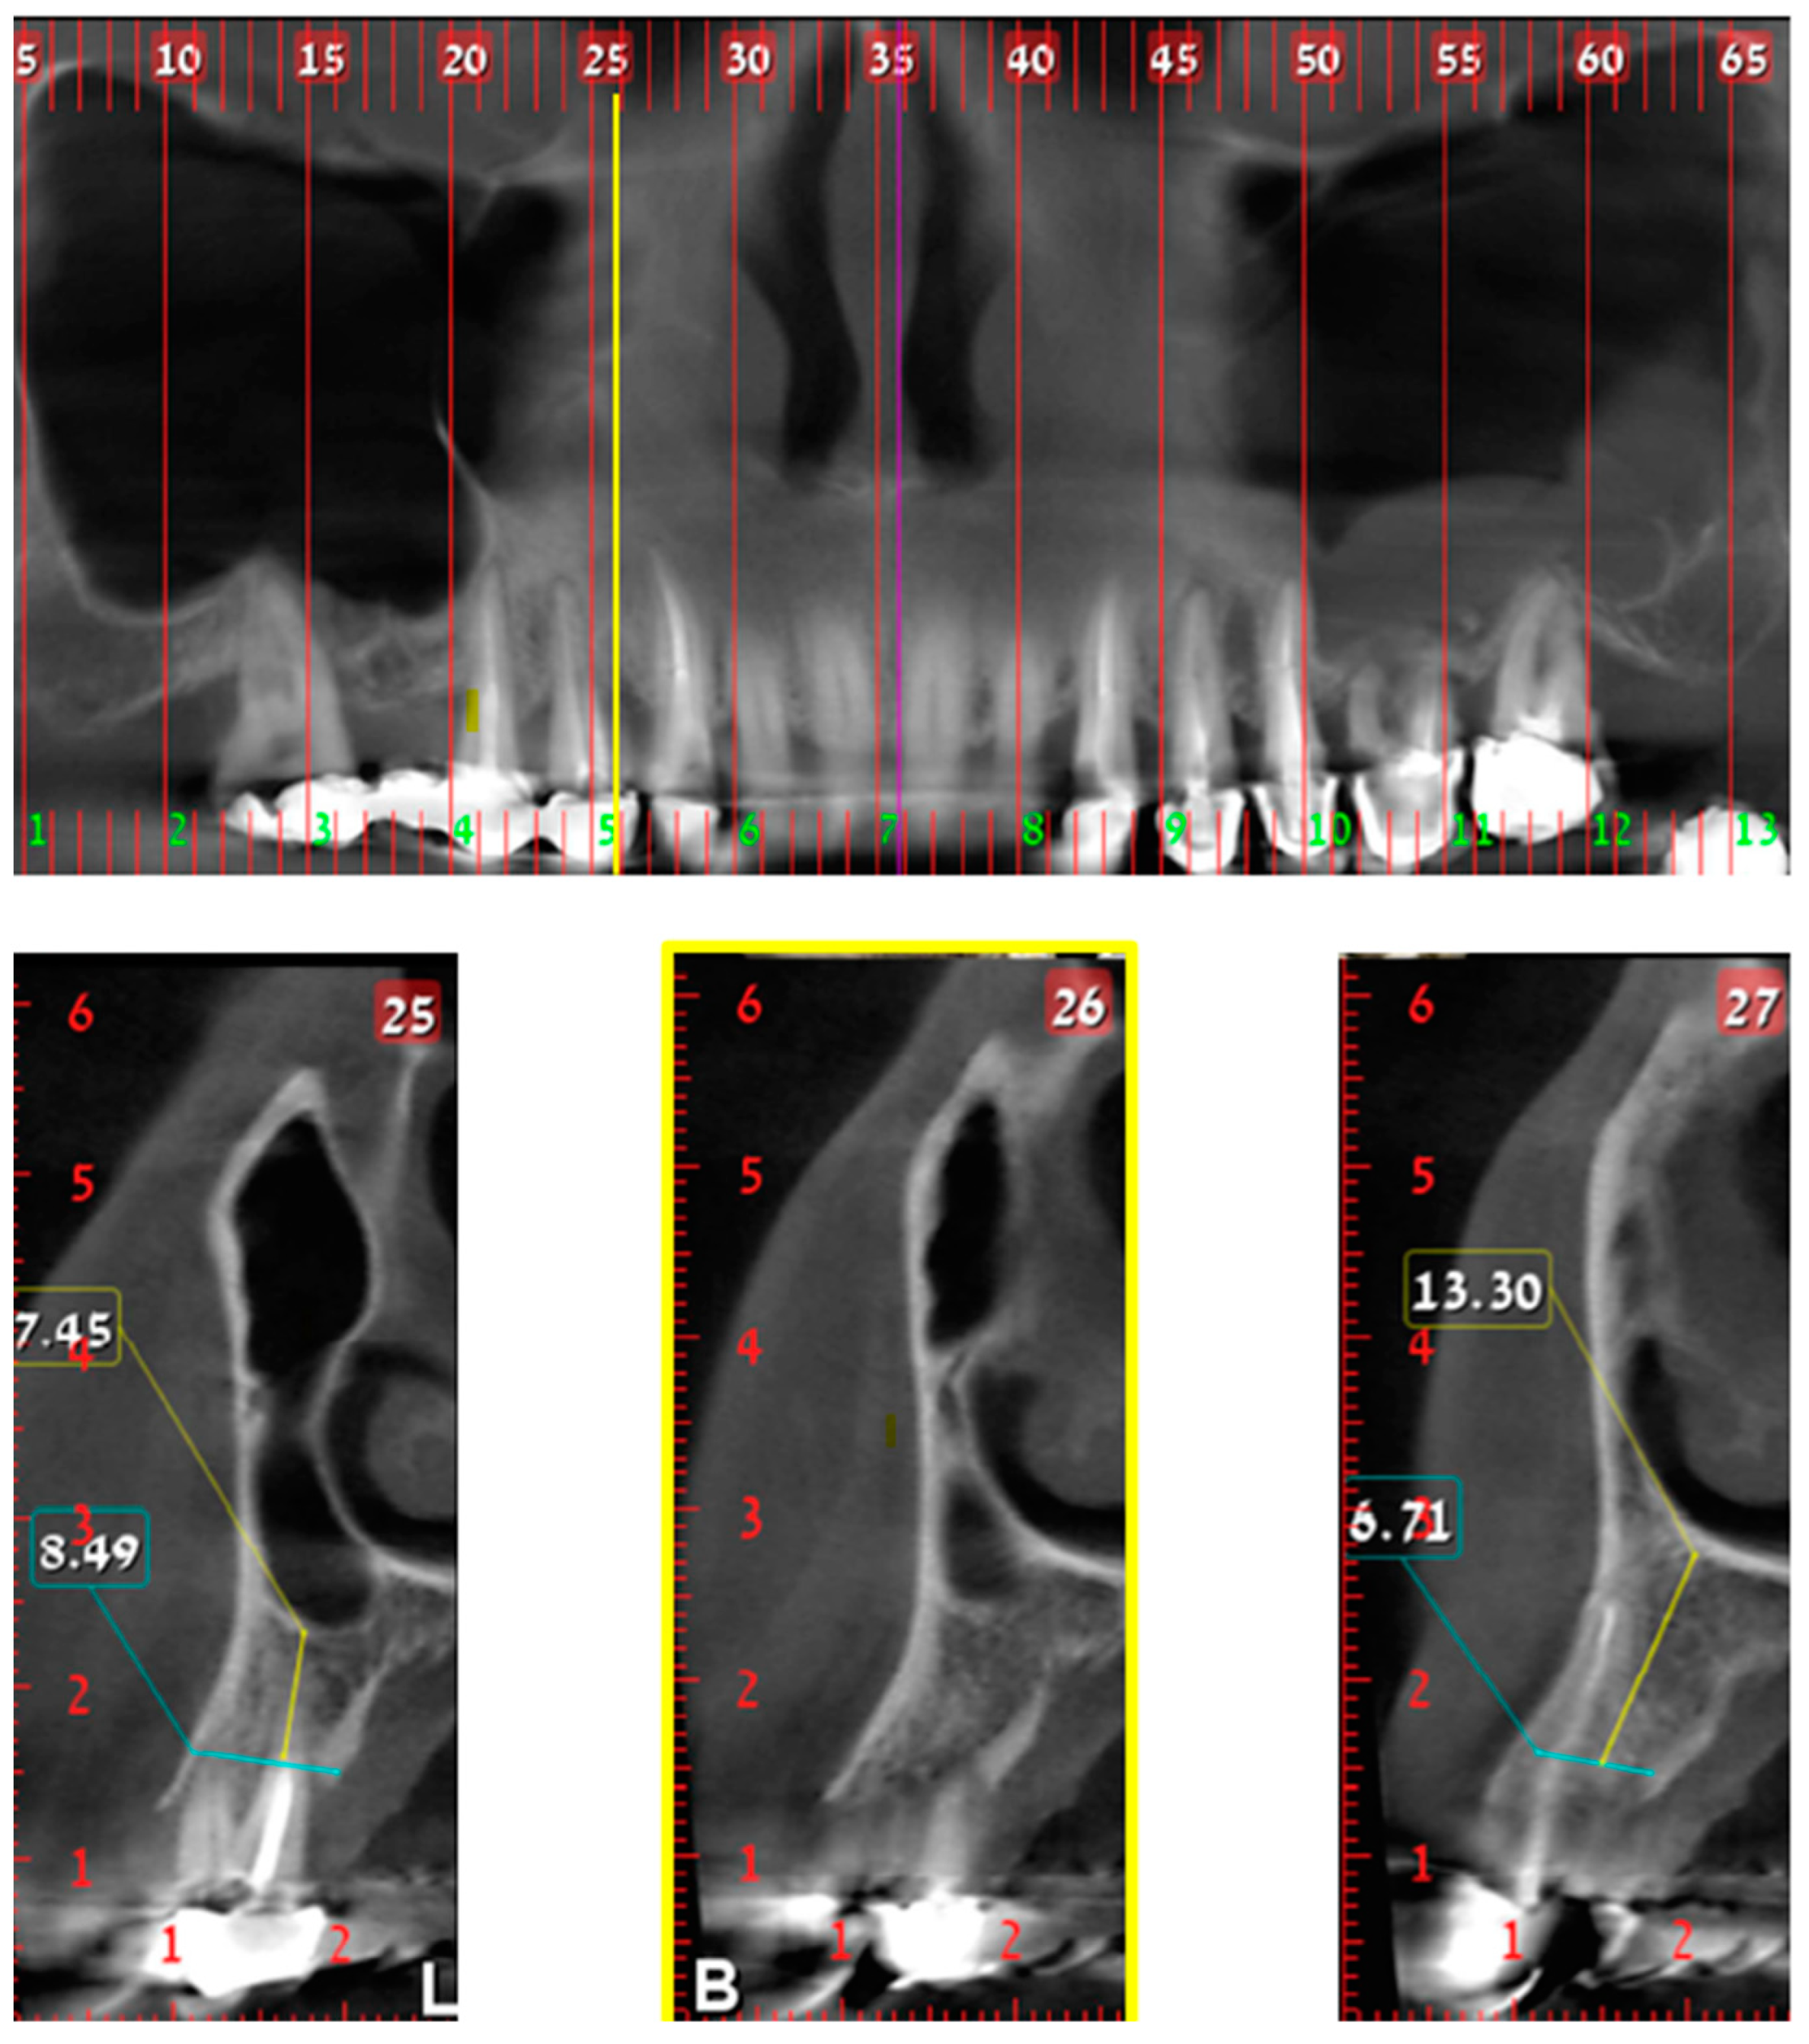

Classes define the MD location of the nasal/sinus border for each hemi maxilla as demonstrate in Figure 1, Figure 2 and Figure 3. The “border cross section” is the most mesial cross section, in reference to maxillary midline, that above the alveolar crest has both nasal cavity and maxillary sinus cavity. The definition of classes is as follows:

Class 1—“border cross section” is located MD up to the distal edge of the canine.

Class 2—“border cross section” is located MD up to the distal edge of 2nd premolar.

Class 3—“border cross section” is located distal to the mesial edge of the 1st molar.

Classes 1 and 2 were defined as normal anatomy and Class 3 as “big-nose variant”.

Figure 1. Class 1; Upper part—CBCT panoramic reconstruction; Lower part—from right to left—CBCT cross sections: cross section number 27—demonstrate nasal cavity alone above the alveolar ridge; cross section number 26—yellow line and frame—demonstrate nasal and maxillary sinus “border cross section”, which is located above the distal part of the canine, defined as Class 1; cross section number 25—demonstrate one cross section distal to the “border cross section”. B, buccal; L, lingual.